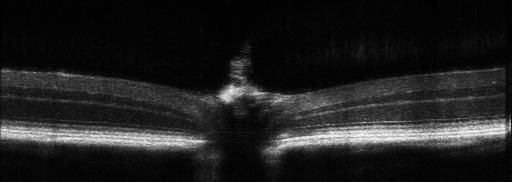

用于眼科动物模型的疾病筛查、病理学、药理学、药效学等方面研究。适用于各项眼科疾病、糖尿病、动脉硬化、高血压、干细胞等研究中视网膜结构的定量变化及定性分析。可对活体动物神经细胞,神经纤维层、微血管等微观结构改变进行早期、实时及长期无损伤的评估。

※ 1.6um高分辨率成像,实现更精准的病变及疗效评估;

2、图像自动分层,实现视网膜8层厚度的自动分析,自动生成对比图表;

应用:眼节OCT成像及定量分析